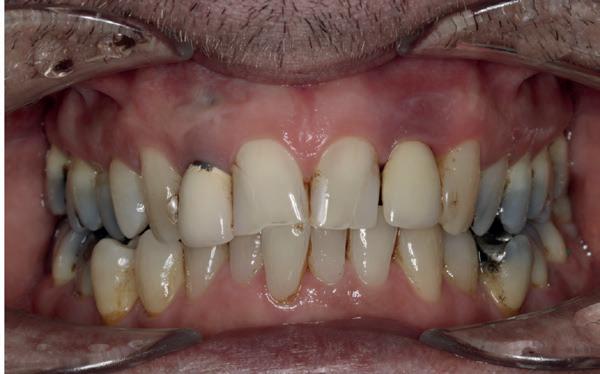

Een 47-jarige vrouw wordt aan het einde van het orthodontische traject door haar eigen tandarts naar mij verwezen voor een intake en eventuele behandeling. Bij mevrouw zijn elementen 12 en 22 afwezig. De 13 en 23 zijn gemesialiseerd. Haar eigen tandarts vraagt of ik het front met composiet kan restaureren om weer een harmonieuze glimlach te krijgen (Afbeelding 1).

Tijdens de intake wordt een complete lichtfoto status gemaakt om de positie van de elementen goed in kaart te brengen en een behandelplan op te kunnen stellen. Op de close-up foto van het bovenfront (afbeelding 2) zien we dat er sprake is van slijtage aan element 11. Elementen 12 en 22 zijn afwezig en elementen 13 en 23 zijn gemesialiseerd. Tussen element 11 en 13 is er sprake van een diasteem. Dit diasteem is niet aanwezig aan de andere zijde (afbeelding 3).

Dit zorgt voor een lastige situatie, omdat bij het sluiten van dit diasteem (dit is de wens van de patiënt) elementen 13 en 11 breder zullen worden dan elementen 21 en 23. Dit is één van de redenen waarom ik patiënten altijd graag aan het einde van het orthodontist traject wil zien. Op dat moment is het nog mogelijk om kleine wijzigingen door te voeren, voordat de beugel definitief wordt verwijderd. Na de intake stuur ik een terugrapportage naar de orthodontist waarbij ik vraag om de elementen zo te positioneren dat de ruimte beter verdeeld is.

Ik zie mevrouw een aantal weken later terug voor evaluatie (afbeelding 4). Er is een klein centraal diasteem ontstaan en daardoor is het diasteem tussen de 11 en 13 ook kleiner geworden. Tussen de 21 en 23 is geen diasteem aanwezig (afbeelding 5), waardoor er hoogstwaarschijnlijk wel iets breedte verschil zal zijn tussen de linker- en rechterzijde.

Met composiet wordt een snelle mock-up gemaakt om te beoordelen of ik in deze situatie goed kan uitkomen met de ruimte, of dat we wellicht de elementen nog meer moeten verplaatsen (afbeelding 6). Mevrouw is zeer tevreden met de snelle mock-up en daarom wordt besloten dat de orthodontische behandeling afgerond kan worden. Eventuele verschillen in breedte kunnen we proberen optisch zoveel mogelijk te maskeren.

Nadat de vaste apparatuur verwijderd is (afbeelding 7 en 8), zie ik mevrouw voor het maken van een afdruk/scan ten behoeve van een wax-up. Aangezien ik in deze casus wil werken met de injectietechniek, is een wax-up noodzakelijk.